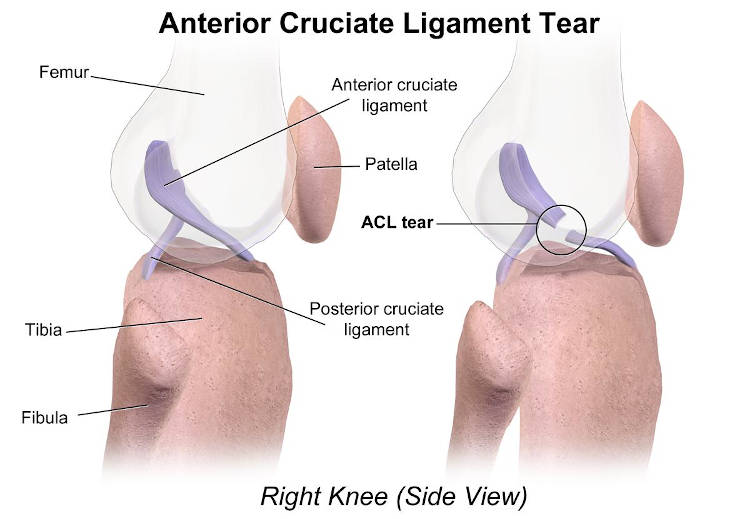

Η έντονη και απαιτητικη αγωνιστική άθληση έχει μετατοπίσει επιδημιολογικά τραυματισμούς που αφορούν μεγαλύτερες ηλικίες και ώριμους σκελετούς σε πολύ νεώτερες, προκαλώντας τον ειδικό ως προς τον τρόπο και χρόνο αντιμετώπισης. Χαρακτηριστική είναι η αύξηση συνδεσμικών τραυματισμών και κυρίως ρήξεων του προσθίου χιαστού συνδέσμου σε πρώιμους εφήβους.

Τίθεται άμεσα το ερώτημα αν πρέπει να χειρουργηθεί ή όχι. Αν υπάρχει αστάθεια και η χειρουργική αναμονή κρίνεται επισφαλής, εγείρονται θέματα χειρουργικής τεχνικής ώστε να επηρεαστεί όσο το δυνατόν λιγότερο ο συζευκτικός χόνδρος από το τούνελ του μοσχεύματος (πιο κάθετο και βραχύτερο). Οι υποτροπές μετά επέμβαση προσθίου χιαστού σε αυτές τις ηλικίες είναι πολλαπλάσιες των ενηλίκων λόγω πιο λεπτού μοσχεύματος και ασυνέπειας στην αποκατάσταση και το χρόνο επανόδου. Σε αυτές τις ηλικίες είναι πιο συχνές και οι αποσπάσεις του συνδέσμου από το μεσογλήνιο έπαρμα της κνήμης που δίνουν τη δυνατότητα να αντιμετωπιστούν σαν αποσπαστικά κατάγματα. Η πρώιμη αποκατάσταση κεφαλικών ρήξεων του προσθίου χιαστού με επανατοποθέτησή του στη μηριαία πρόσφυσή του (Internal brace), έχει μεγαλύτερη ένδειξη σ’ αυτές τις ηλικίες.

Επίσης συχνότερη είναι και η αποκατάσταση μερικής ρήξης του συνδέσμου συντηρητικά σε σχέση με τους ενήλικες.

Επίσης συχνότερη είναι και η αποκατάσταση μερικής ρήξης του συνδέσμου συντηρητικά σε σχέση με τους ενήλικες.